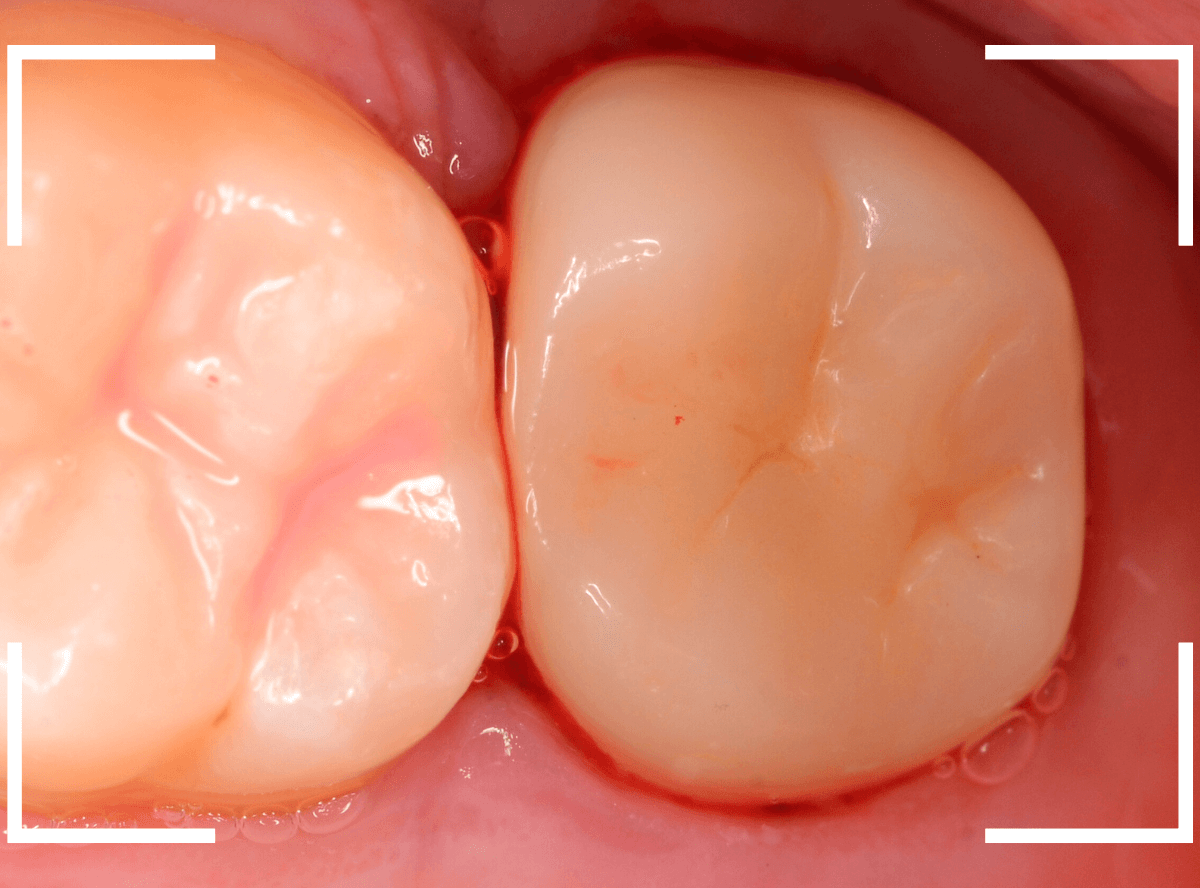

歯の裏側の大きな虫歯を処置した方です。

白いセメントで埋まっている部分が虫歯の処置をした部分なのですが、虫歯が大きく、歯の2/3くらい削る必要がありました。

しばらく経過観察したのですが、特に症状もなかったとの事でしたので、歯の形をトリミングして、型どりにはいる段階です。